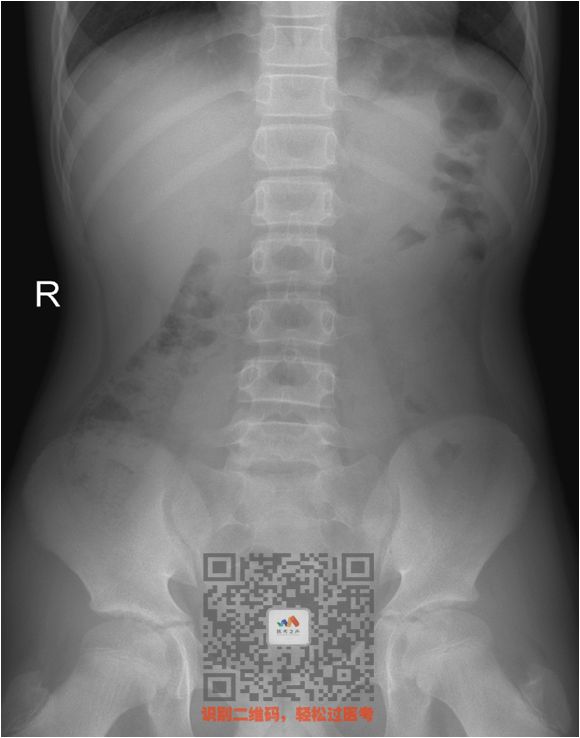

二、腹部X线平片

① 正常腹部平片

一眼看上去,干干净净

没有膈下游离气体(黑影)

没有液气平,没有结石影

看图

上面片子中间有点肠道气体

这是正常的屁,不要误认为梗阻